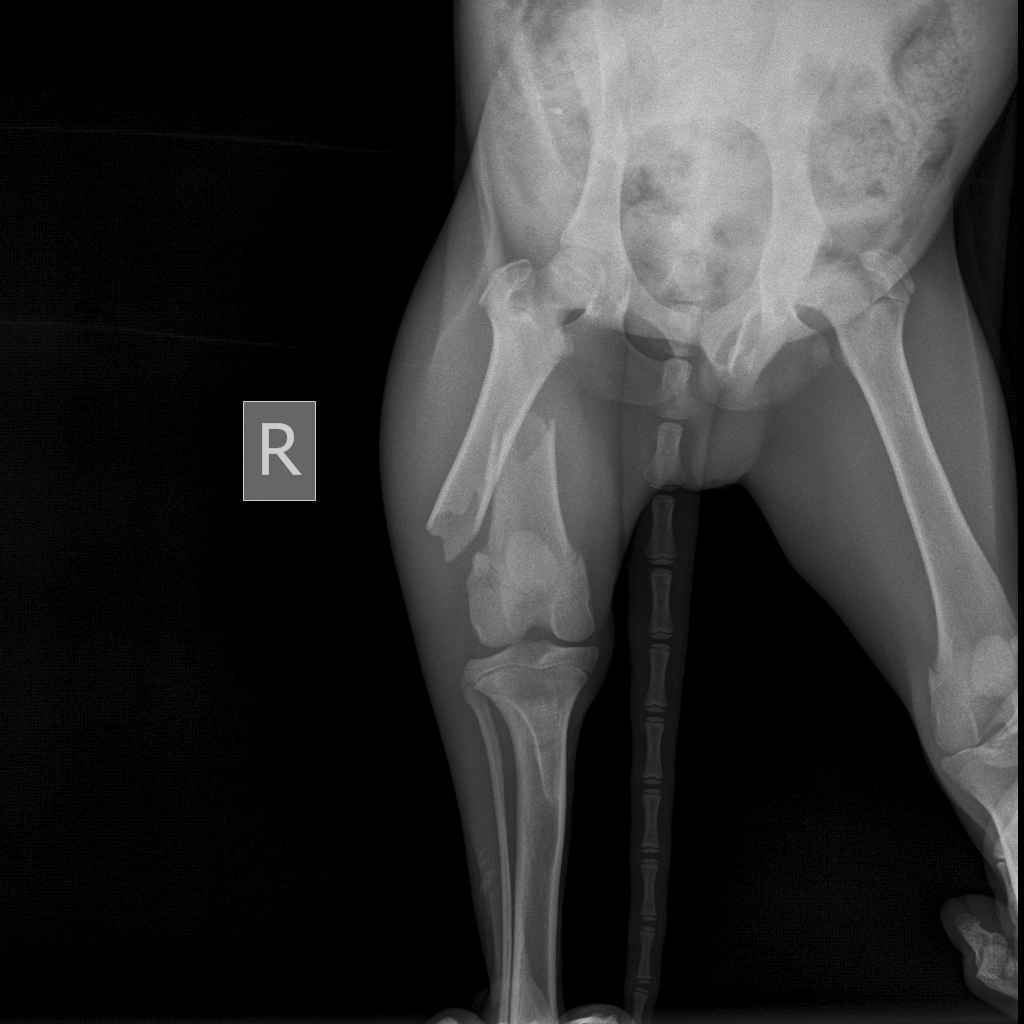

Щенка с поломанной ногой в морозную погоду оставили привязанным в поле. Его заметил 28 января житель Ольшанки и сообщил волонтёрам. В клинике сообщили, что животное сильно истощено, у него сломано бедро. Возможно, его кто-то систематически избивал.